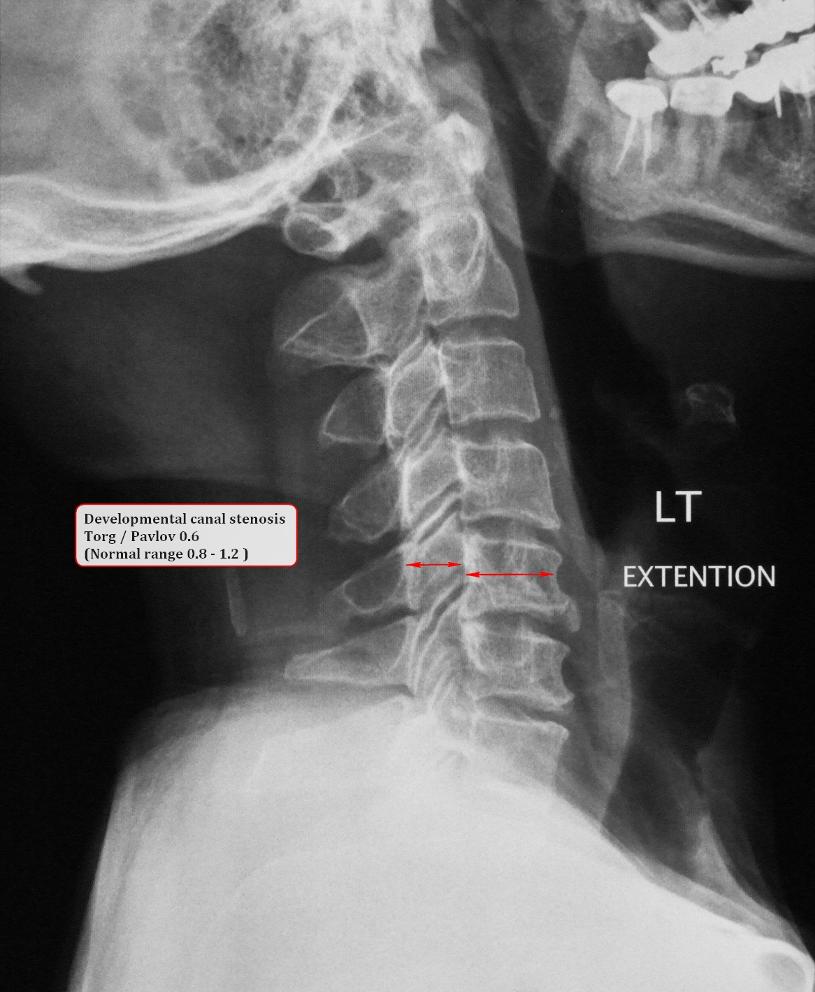

Acute cervical cord injuries caused by hyperextension of without fracture or dislocation of the cervical spine. In the present study, Pavlov H, Torg JS, Robies MS, et al: Cervical spinal stenosis: determination with vertebral body ratio method. Radiology 164:771–775, 1987 ... Access Full Source

Cervical Spondylotic Myelopathy - Siemionow

Cervical spondylotic myelopathy is a slowly progressive process resulting from age related spinal defects, progressive degenerative changes, acute cervical disc herniation Congenital(present at birth), or developmental canal stenosis may be an underlying contributor to many, but ... Document Retrieval